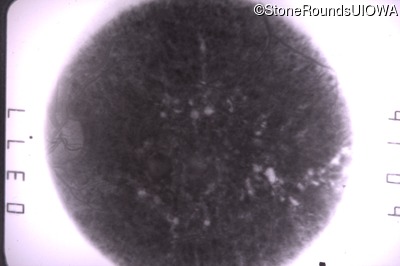

Optical Coherence Tomography - Right - 20/20 -2 sc

Exemplar / OCT Stack